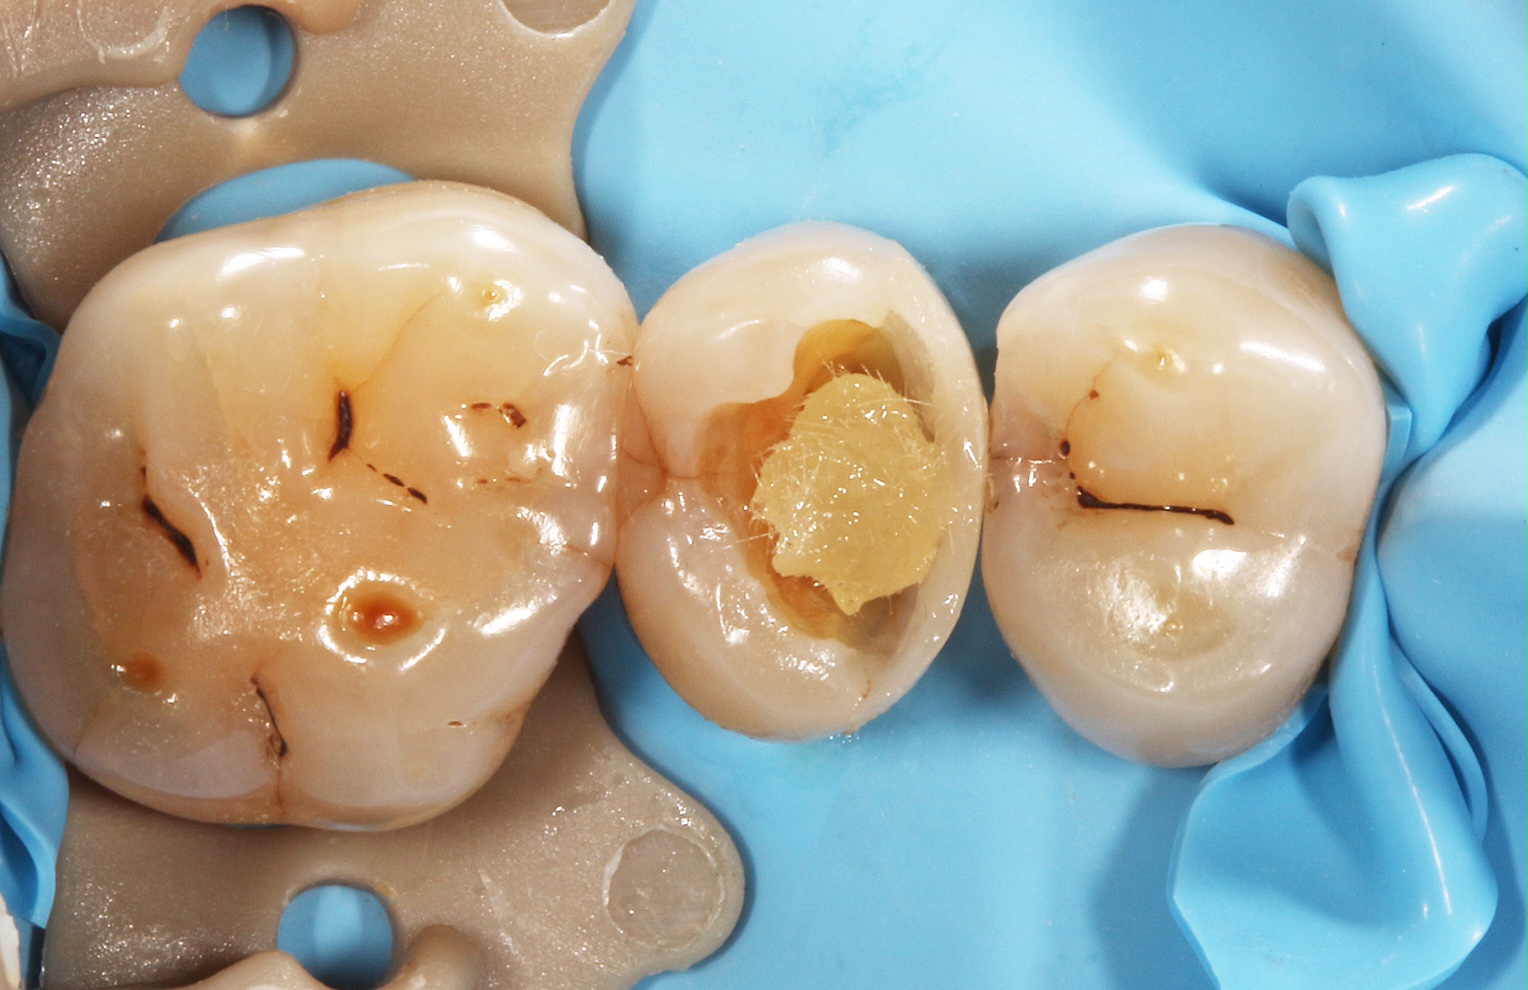

Klinik Vakalarla Kanal Tedavili Posterior Dişlerin Estetik Restorasyonu

"Klinik Vakalarla Kanal Tedavili Posterior Dişlerin Estetik Restorasyonu" başlıklı uygulamalı eğitimin yeni programı 7 Nisan 2018 tarihinde İstanbul Kadıköy'de gerçekleştirilecek.

“Klinik Vakalarla Kanal Tedavili Posterior Dişlerin Estetik Restorasyonu” eğitimi konu ilgili çalışmaları ilgiyle takip edilen Yrd. Doç. Dr. Bora Korkut ve Dr. Toygan Bora tarafından verilecek. GC Türkiye tarafından desteklenen uygulamalı eğitim, 7 Nisan tarihinde İstanbul Kadıköy’de gerçekleştirilecek.

Bu eğitimde diş kliniğinde en çok karşılaşılan problemlerden biri olan kanal tedavisi görmüş posterior dişlerde doğru restorasyon seçimi ve uygulamaları ile ilgili klinik vakalar üzerinden detaylı anlatım yapılacaktır.

Posterior dişlerde kanal tedavisi sonrası kalan diş dokusuna göre hangi tip restorasyonun tercih edilmesi gerektiği ve uygulaması klinik vakalar üzerinden tartışılarak anlatılacaktır. Katılımcılara ayrıca posterior dişlerde endodontik tedavide başarı kriterleri ve posterior direkt estetik kompozit tabakalaması ile ilgili detaylı bilgi verilecektir.

Pratik eğitim ise iki bölümden oluşacak olup birinci bölümde kanal tedavisi uzmanı Dr. Toygan Bora tarafından tüm detaylarıyla bir posterior dişe kanal tedavisi uygulaması yapılacaktır. İkinci bölümde ise restoratif diş tedavisi uzmanı Yrd. Doç. Dr. Bora Korkut tarafından tüm katılımcılarla senkronize şekilde adım adım bir posterior dişe direkt estetik kompozit tabakalama uygulaması yapılacaktır.